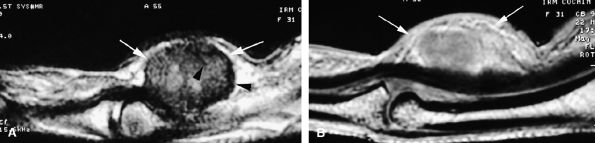

![]() |

FIGURE 11.6 ● Stener's lesion. The ulnar collateral ligament (UCL) is torn from its distal insertion and the proximal end passes over the expansion of the adductor pollicis aponeurosis and cannot heal.

FIGURE 11.7 ● Coronal post-contrast T1-weighted image showing a nondisplaced tear of the UCL of the first metacarpophalangeal joint (MP) joint. The torn UCL is elongated beneath the adductor aponeurosis (AA). There is focal enhancement of the tear (asterisk). 1 MC, first metacarpal.

FIGURE 11.8 ● MR arthrography of nondisplaced tear of the UCL of the first MP joint. Coronal (A) and sagittal multiplanar reformatted (MPR) (B) T1-weighted fat-suppressed 3D gradient-echo images showing an oblique tear (asterisk) of the UCL without avulsion. Thearrows mark the distal (black) and proximal (white) aspects of the torn UCL. The sagittal MPR slice is defined along the course of the UCL. MC, metacarpal; AA, adductor aponeurosis.

The UCL lies deep to the overlying low-signal adductor aponeurosis on coronal images (Figs. 11.7 and Fig. 11.8). In a nondisplaced partial or complete tear of the UCL, the ligament appears thickened all along its course, sometimes with a small gap. When displaced, the UCL appears as a proximally retracted round or stump-like structure, which demonstrates low signal on all sequences. It is no longer parallel to the long axis of the thumb and presents an increased horizontal orientation.

Stener's lesion may present with a “yo-yo on a string” pattern, with the retracted and balled-up UCL representing the yo-yo and the more distal linear adductor aponeurosis representing the string (Fig. 11.9).

On axial images, the ligament may be seen lying above or intersecting the adductor aponeurosis.